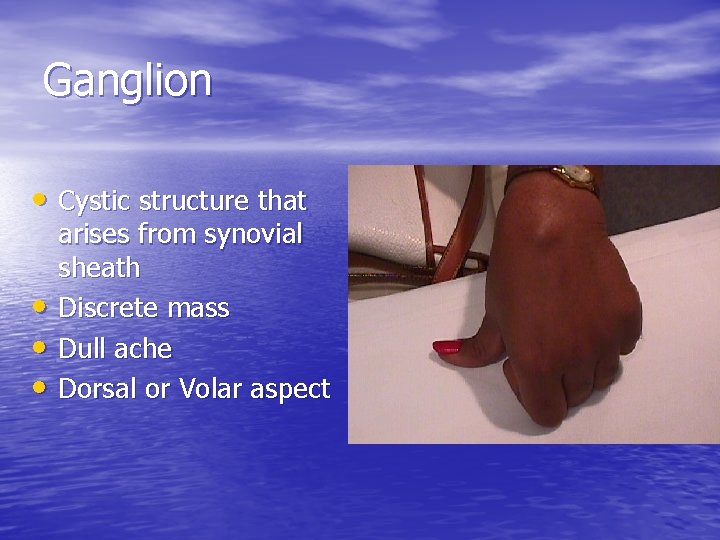

Ganglion • Cystic structure that • • • arises from synovial sheath Discrete mass Dull ache Dorsal or Volar aspect